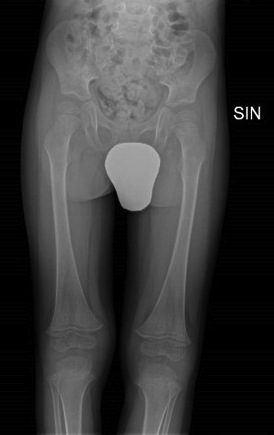

Paziente 4 - Maschio di 3 anni con riferito improvviso rifiuto della deambulazione. La RM encefalo e midollo risulta negativa mentre la RM del bacino e la scintigrafia mostrano un quadro suggestivo di sacroileite. Da una più accurata anamnesi emerge che il bambino ha un’alimentazione estremamente selettiva per cui si ipotizza un difetto vitaminico. Effettua quindi Rx arti inferiori che mostra bande di radiotrasparenza e ispessimento della corticale (Figura 3). Il dosaggio della vitamina C conferma la diagnosi di scorbuto.